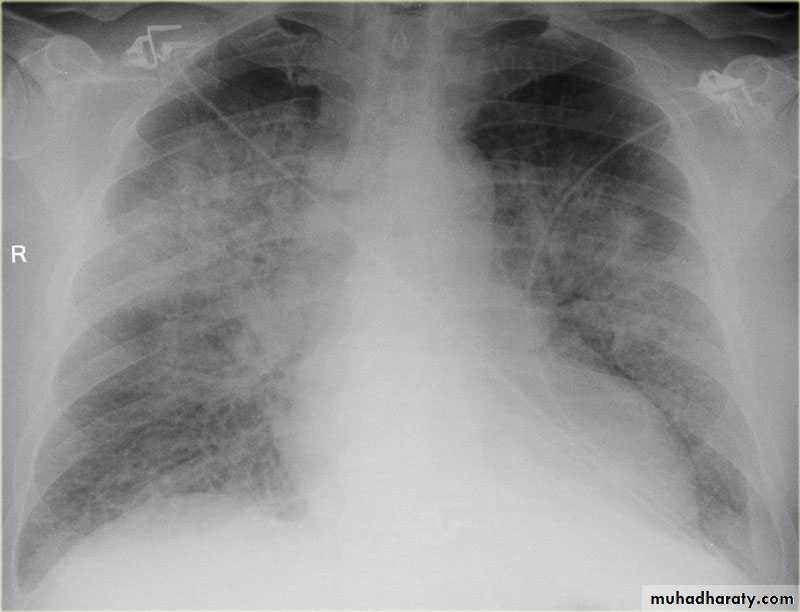

Lymphoma is a malignancy arising from lymphocytes or lymphoblasts. Lymphoma can be restricted to the lymphatic system or can arise as extra nodal disease. This, along with variable aggressiveness results in a diverse imaging appearance.

Nodal disease

Hodgkin's disease is usually almost entirely confined to the lymph nodes.

Extra nodal disease

Extra nodal HD although uncommon may be found in any organ system, either as a primary manifestation or as dissemination of systemic disease.

Hodgkin lymphoma of te middle mediastinum